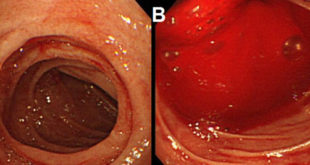

Viêm đại tràng là tình trạng đại tràng bị viêm nhiễm. Bệnh viêm đại tràng ảnh hưởng nhiều đến sức khỏe người bệnh. Đại tràng là nơi hấp thụ nước và muối khoáng từ thức ăn và cùng với sự phân hủy cùng các vi khuẩn tạo bã thức ăn thành phân, khi đủ lượng đại tràng sẽ co bóp …

Viêm đại tràng co thắt là gì? Viêm đại tràng co thắt được định nghĩa là hội chứng kích thích ruột hay rối loạn chức năng của đại tràng, bệnh gây ra những triệu chứng rất khó chịu như đầy hơi, đau quặn bụng, tiêu chảy hoặc táo bón… kéo dài ít nhất 3 tháng mà không làm thay đổi …

Bệnh viêm đại tràng nguyên nhân và triệu chứng. Bệnh viêm đại tràng là bệnh thường gặp ở đường tiêu hóa, một bệnh phổ biến với tỉ lệ người mắc rất cao, bệnh dễ tái phát và có thể gây nên những biến chứng nguy hiểm tới tính mạng con người như ung thư hóa hay thủng đại tràng nếu …